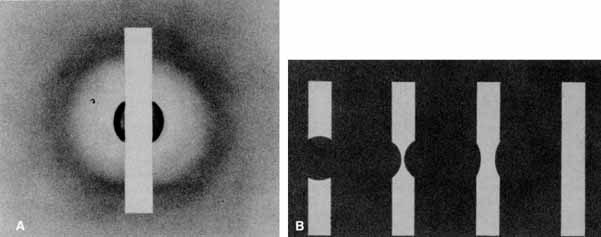

Functional testing has been used to help differentiate pseudoholes or other lesions from true macular holes. The Watzke-Allen sign was one of the first such functional tests.14 This test is performed by presenting a narrow slit beam over the suspected macular hole. The patient is then asked to describe what he or she perceives. If the patient describes a break in the line, a full thickness hole should be suspected (Fig. 1). Another method of performing this test is to pass the slit beam slowly over the macula from varying angles. If the patient perceives a break in the line, at any time, the test is considered to be positive (i.e., there is a full-thickness macular hole).